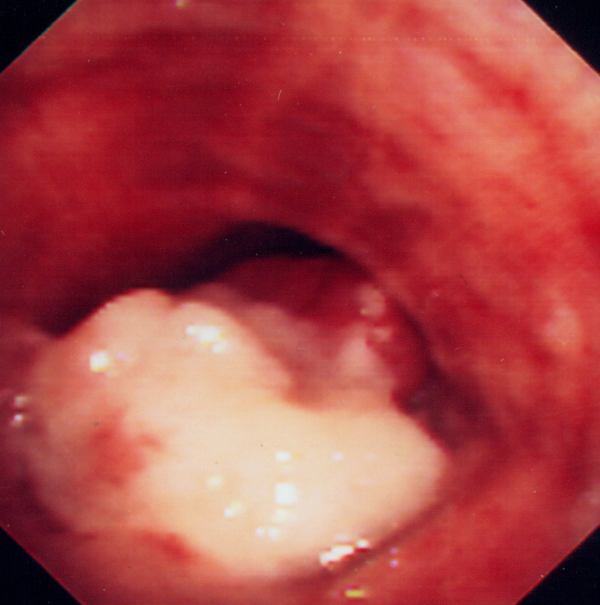

What is shown on this bronchoscopy?

Fungating mass invading the bronchial lumen = malignant bronchial tumour